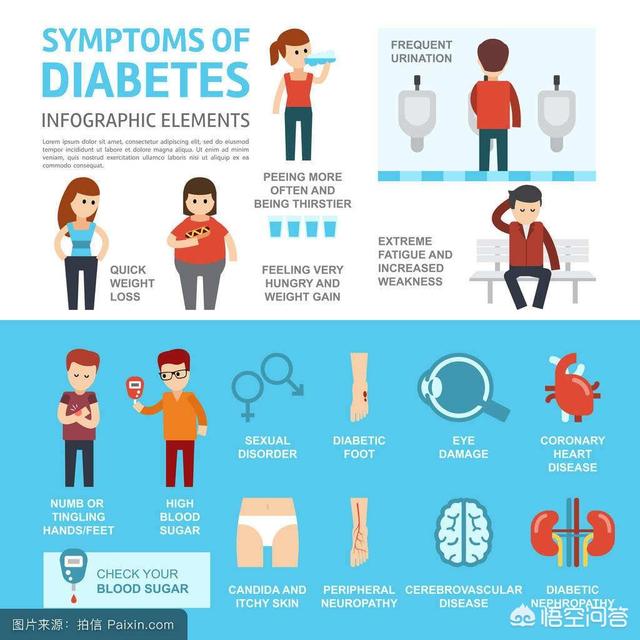

糖尿病は主に、多尿、多飲、多食、体重減少によって現れる。

多くの患者は糖尿病であることに気づかず、合併症が現れて初めて病院で検査を受ける。例えば、尿路感染症、目のかすみ、動悸や息切れ、さらにはケトアシドーシスのような重篤な状態まで。

一般的な症状患者は無気力、体力低下、過敏性を示す。さらに、体のかゆみが視覚障害として現れることもあり、しばしば手足のしびれや針や針のような感覚を伴い、足潰瘍を合併することもある。女性では月経痛や無月経などの症状がみられ、男性ではインポテンツや性欲減退が最も多くみられる。

糖尿病の症状は?

糖尿病の主な臨床症状には、多尿、多飲、多食、体力・体重の低下(一般に「三多及び一少」と呼ばれる)、食前低血糖、皮膚のかゆみ、皮膚感染症へのかかりやすさ、視力の低下、糖尿病の慢性合併症として、手足のしびれ、パニック発作や息切れ、下痢や便秘、尿閉、勃起不全(「インポテンス」と呼ばれる。)インポテンス)などの糖尿病の慢性合併症の症状。